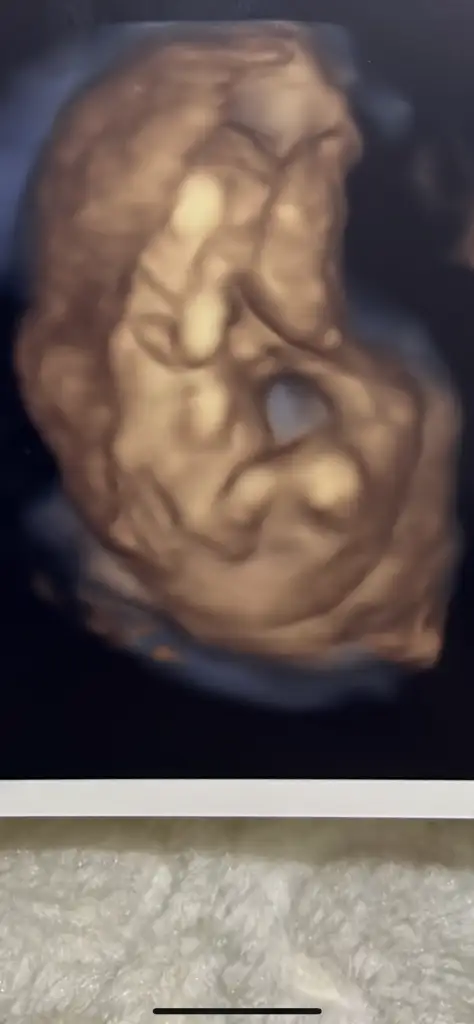

Bana da bakar mısın :)))

Eklentiler

• C1B8836F-5D80-4617-98FE-F56B56D15A4D.webp

27,2 KB · Görüntüleme: 64